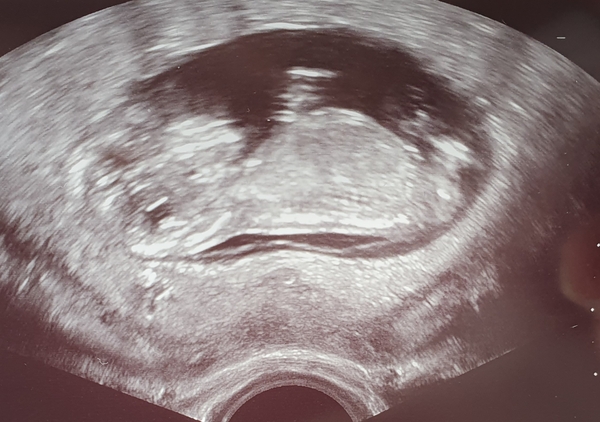

12 week scan done! Currently in the waiting area to get my bloods taken, but everything developing ok, and a very wriggly baby! I'm 12 weeks rather than 12+2 as I originally thought, due 25th May 2020! Exciting to finally have an official due date and know everything is ok, the anxiety has been crazy!!

@TwinklyTwinkle that has to be one of the best scan photos from 12 weeks i've ever seen! Glad everything is ok and hopefully the anxiety will settle now!

@TwinklyTwinkle eeek amazing pic, crystal clear you must be super excited!!! Also thats funny that you thought that you were 12+2 and now you're 12 as I've got the exact opposite!

@mumofbun @PrinnyPree Thanks guys! It took the sonographer a while to get the photos and do the measurements, I think he wanted to get a good one!